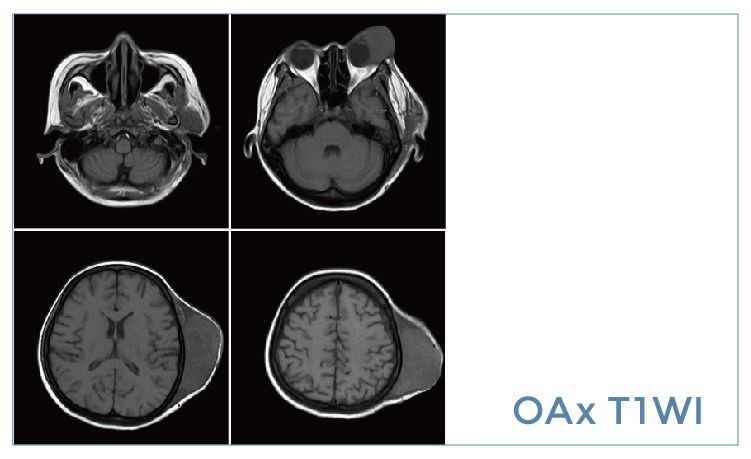

【朗润影像档案】20190920磁共振影像病例结果讨论